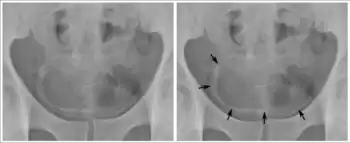

Calcifications on bladder wall caused by urinary schistosomiasis

Cystitis refers to infection or inflammation of the bladder. It commonly occurs as part of a urinary tract infection.[25] In adults, it is more common in women than men, owing to a shorter urethra. It is common in males during childhood, and in older men where an enlarged prostate may cause urinary retention.[25] Other risk factors include other causes of blockage or narrowing, such as prostate cancer or the presence of vesico-ureteric reflux; the presence of outside structures in the urinary tract, such as urinary catheters; and neurologic problems that make passing urine difficult.[25] Infections that involve the bladder can cause pain in the lower abdomen (above the pubic symphysis, so called "suprapubic" pain), particularly before and after passing urine, and a desire to pass urine frequently and with little warning (urinary urgency).[25] Infections are usually due to bacteria, of which the most common is E coli.[25]